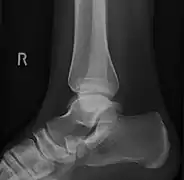

From left to right: Type 1, 2 and 3

Lateral projection of type 2